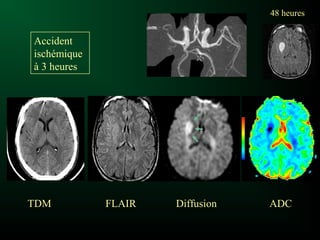

IRM plus sensible que le scanner :

– Diagnostic plus précoce

– Infarctus de petite taille

– Etendue et gravité de l’infarctus dès les premières

heures (diffusion, perfusion)

Thrombolyse si <4.5h

IRM et ischémie

Séquence de diffusion+++

- positive précocement

- sensible

- spécifique

Principe :

Mesure la mobilité de la molécule d’eau dans un tissu

Dans le tissu ischémié, à la phase précoce, l’eau est

« piégée » dans les cellules : la mobilité des molécules

d’eau est moindre

Ischémie récente =

hypersignal en diffusion et

diminution du coefficient de diffusion

Coefficient de diffusionHypersignal diffusion

48 heures48 heures

TDMTDM FLAIRFLAIR DiffusionDiffusion ADCADC

Accident

ischémique

à 3 heures